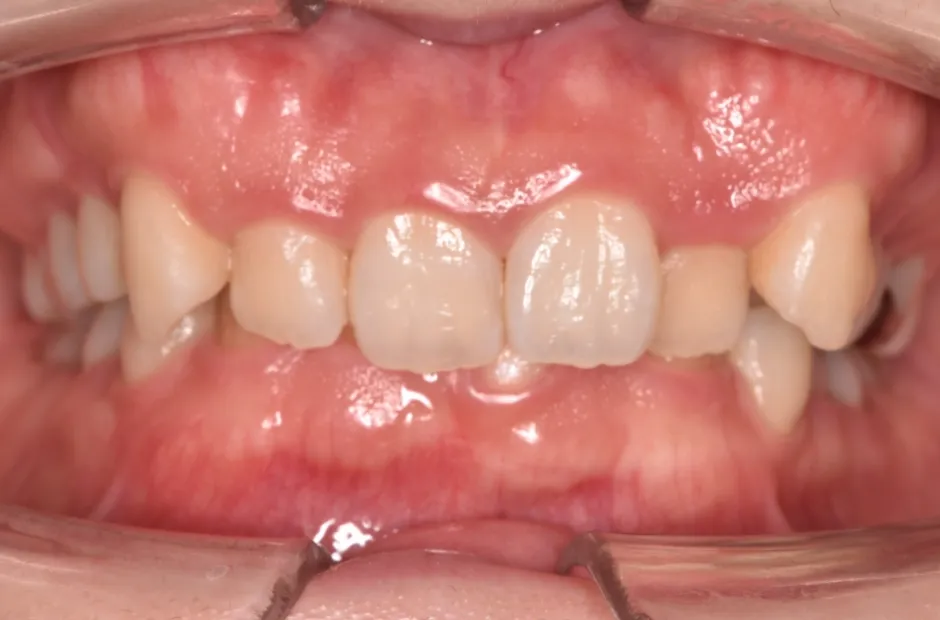

| 診断名・主訴 | 下顎前突、叢生 |

|---|---|

| 年齢・性別 | 23歳・女性 |

| 治療期間・回数 | 3年 |

| 治療に用いた主な装置 | 上顎5,5 下顎4,4 |

| 抜歯部位 | 舌側矯正 |

| 治療費 | 100万円(税抜) |

| リスク・副作用 | 装置による違和感・疼痛・歯肉退縮・歯根吸収・虫歯のリスクなど |

治療前